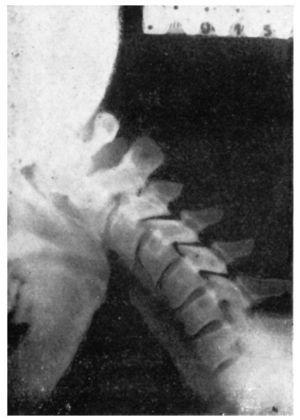

Figura 7 A.Caso núm. 6. M. Y. F. Inestabilidad de la quinta vértebra cervical.

Figura 7 B.Caso núm. 6. M. Y. F. Inestabilidad de la quinta vértebra cervical.

Figura 7 C.Caso núm. 6. M. Y. F. Comprobación a las cuatro semanas de la intervención. Bloque compacto de las 4, 5 y 6a C.